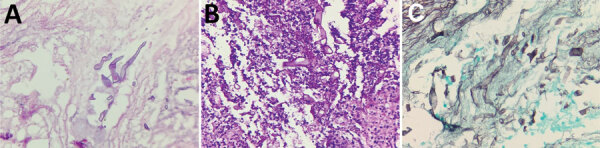

Description:We provide an overview of the epidemiology and clinical course of mucormycosis in the coronavirus disease (COVID-19) pandemic era. We conducted a retrospective chart review of 178 patients with clinical or diagnostic, endoscopically or histopathologically confirmed rhino-sino-orbital or cerebral mucormycosis after COVID-19 treatment during the second wave of COVID-19 in Pune, India. Median time to symptom onset from COVID-19 detection was 28 days. Moderate or severe COVID-19 was seen in 73% of patients and diabetes in 74.2%. A total of 52.8% received steroids. Eschar over or inside the nose was seen in 75%, but baseline clinical and laboratory parameters were mostly unremarkable. Bone penetration was present in ≈90% of cases, 30% had soft-tissue swelling of the pterygopalatine fossa and 7% had cavernous sinus thrombosis, and 60% had multifocal mucormycosis. Of the 178 study cases, 151 (85%) underwent surgical debridement. Twenty-six (15%) died, and 16 (62%) of those had multifocal mucormycosis.